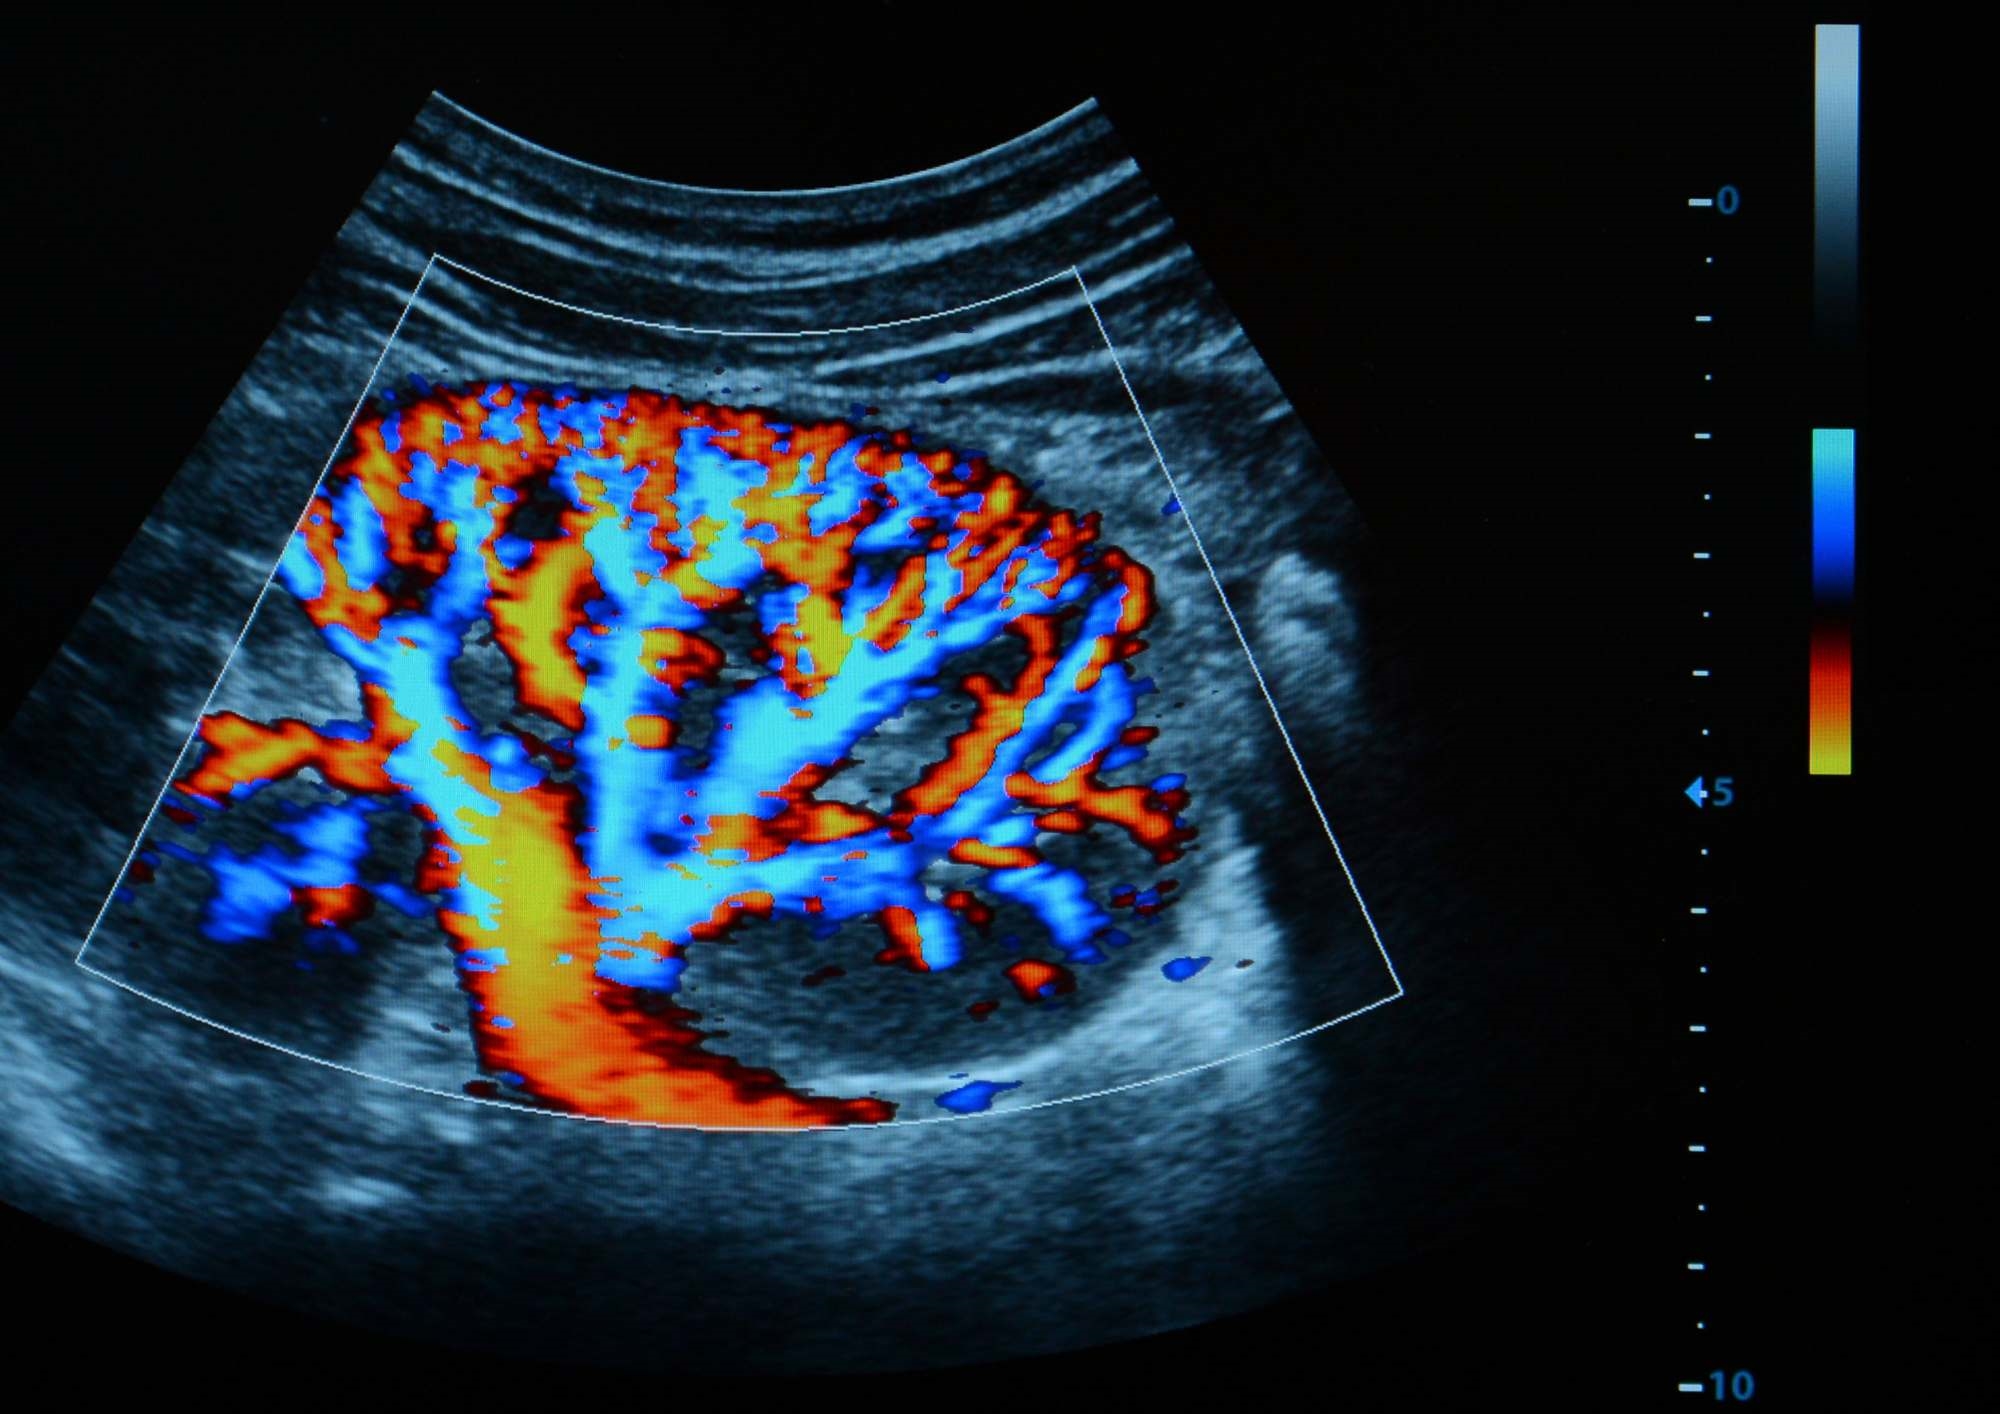

A Doppler Ultrasound can look for the presence of deep venous thrombosis

What does a Doppler Ultrasound Scan show?

A Doppler Ultrasound Scan assesses the amount of blood flowing through blood vessels in the arteries and veins in the legs. A Doppler Ultrasound, combined with a regular Ultrasound, takes images of the lower limbs to enable doctors to evaluate how well the blood is circulating and to look for the presence of deep venous thrombosis (DVT) clots.

This type of scanning is used when a DVT (Deep Vein Thrombosis) is suspected. A DVT occurs when a large clot forms in a vein in the leg, restricting or stopping blood flow. If you have been experiencing pain or swelling of the calves or ankles then you can request a Doppler Ultrasound Scan to diagnose or rule out a DVT.

A Doppler Ultrasound Scan can also assess blood flow through the arteries in the legs, to look for areas of atherosclerosis, which is when fatty substances cause arteries to narrow. Atherosclerosis can cause Peripheral Vascular Disease (PVD), which can cause leg pain as the blood supply to the legs is restricted. A Doppler Scan can also evaluate the effect of arterial grafts.